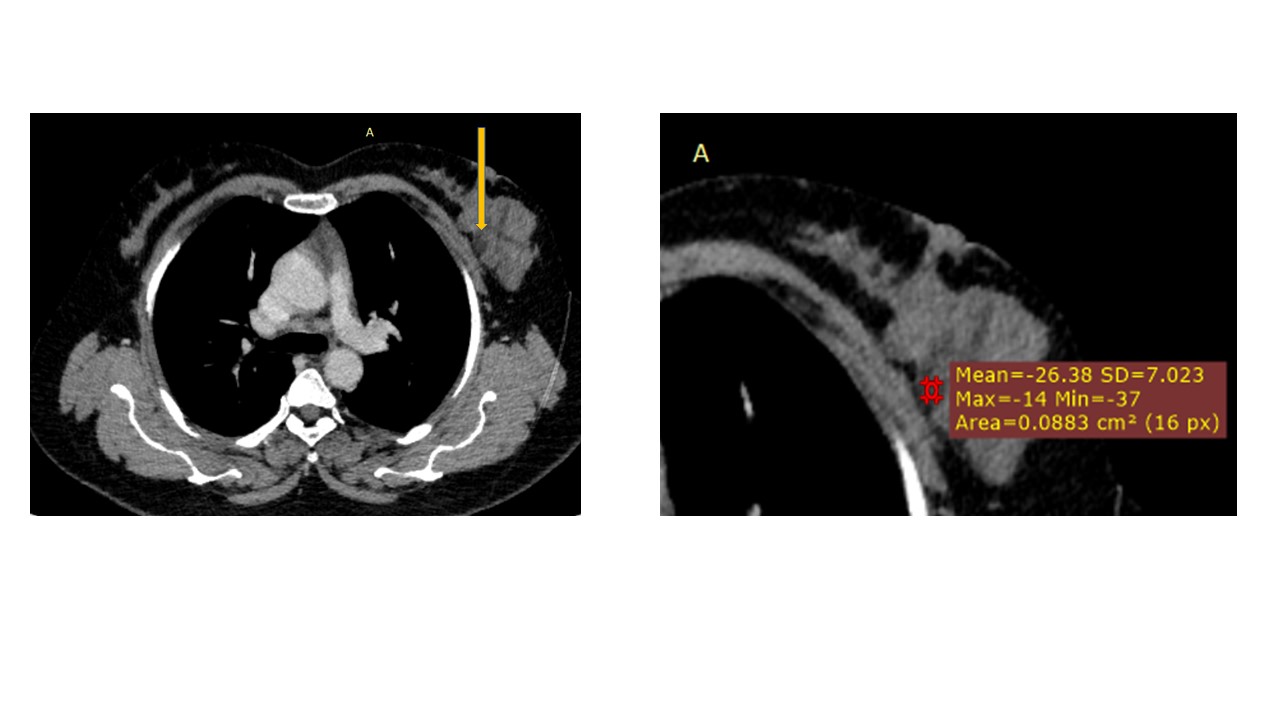

Physical examination revealed a 6.0?×?5.0 cm mass in the left breast. Mammography demonstrated an irregular, fat-containing, heterogeneous mass with circumscribed margins in the upper outer quadrant of left breast. Few scattered foci of coarse calcification were present within the mass. Breast sonography revealed an irregular, parallel, hyperechoic mass with circumscribed margins and no posterior acoustic features in the left breast at 3 o’clock position. Mild vascularity was observed on Color Doppler imaging. Contrast enhanced ultrasound (CEUS) done out of academic interest showed ill-defined, heterogenous enhancing mass, showing irregular shape, having surrounding vessels. Quantitative analysis showed higher PI (pulsatility index), AUC (area under curve) and lower TTP (time to peak) compared to normal tissue. The mass was assessed as Breast Imaging Reporting and Data System category 4b, and ultrasound-guided 14-gauge core biopsy revealed a biphasic tumor composed of bilayered ductal epithelium compressed by the proliferating stroma into leaf like architecture, The stromal cells showed increased cellularity, marked nuclear atypia and pleomorphism with round to oval nuclei, opened up chromatin, prominent nucleoli and moderate to abundant cytoplasm with many bizarre looking tumor giant cells. The stroma showed extensive heterologous lipomatous differentiation composed of neoplastic adipocytes as well as few lipoblasts. Mitosis was 3-4/10/hpf. Final histopathological diagnosis of malignant Phyllodes tumor with liposarcomatous differentiation was given. CT scan chest was done to look for lung metastasis, which revealed an irregular soft tissue mass in left breast with internal focal areas of fat attenuation. No nodules were seen in the lungs. Subsequent lumpectomy was performed and the gross specimen showed a well-demarcated tumor, measuring?6.8?×?6.5 × 3 cm. There were considerable bright yellow fatty components and some cleft-like spaces. Microscopically, the tumor exhibited a typical leaf-like growth pattern with extensive stromal overgrowth and stromal hypercellularity. Extensive areas of lipomatous differentiation were seen ranging from mature adipocytes to lipoblasts showing marked stromal atypia and irregularity. Mitotc activity was 7-8/10hpf. IHC for MDM2 was negative. Overall features were of malignant phyllodes tumor with well differentiated liposarcomatous differentiation.